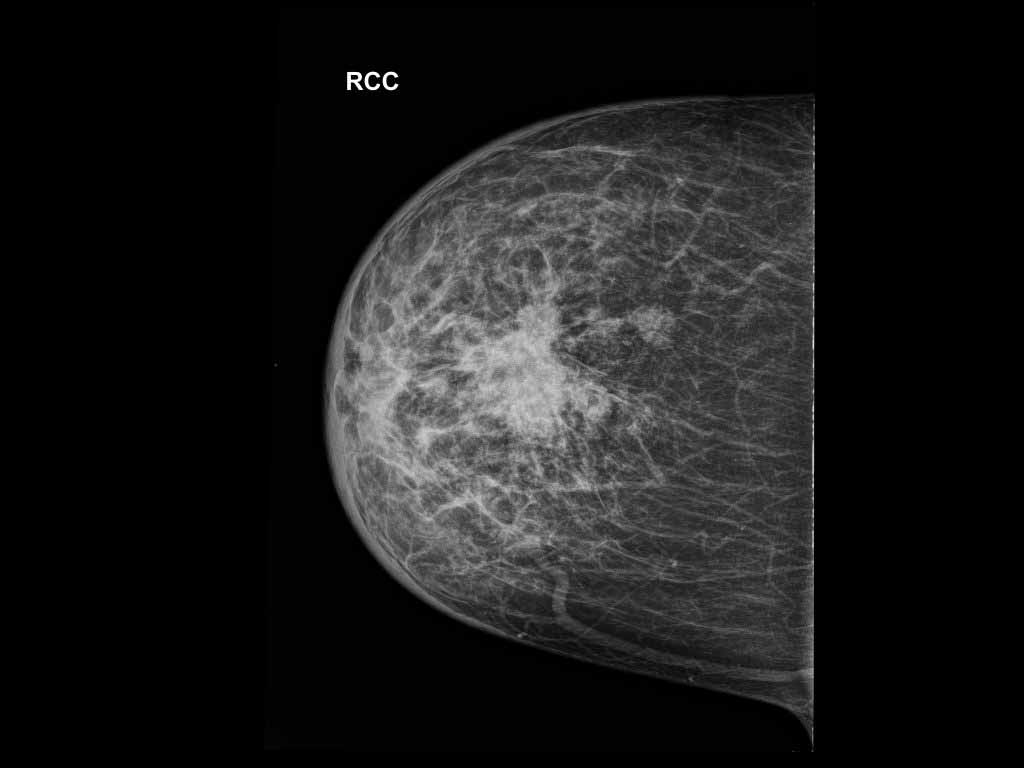

Kesesuaian Kategori Bi Rads Mamografi Dengan Pemeriksaan Histopatologi Di Rs Kanker Dharmais Tesis Pdf Download Gratis

Http Lib Ui Ac Id File File Digital 20367141 Sp Yulia 20rachmawati Pdf

Http Lib Ui Ac Id File File Digital 20367141 Sp Yulia 20rachmawati Pdf

Bab 2 Ca Mammae